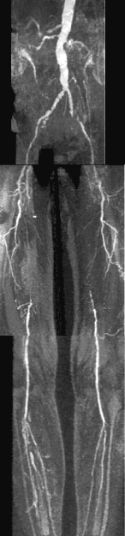

CE-MRA of the aortic arch and great vessels (left) into the brain, renal arteries (top), selective carotid bifurcation (top right) showing ICA/ECA stenosis, and 3-section run-off (very right) showing multiple stenoses, including long-segment bilateral SFA stenoses.

CE-MRA is a fairly new, non-invasive MR technique that utilizes ultra fast MR sequences to obtain exquisite MRA images. These images are obtained during intravenous administration of only 20-30 cc of Gadolinium using an MR-compatible power injector. A bolus-tracking software tracks the bolus of contrast for optimal timing. Subtraction techniques may also be utilized for improved tissue contrast. Thus, a high-end scanner is required to perform the procedure.

The actual scan is performed in one breath hold (about 20 seconds), but of course it takes some time to prepare the patient and set up the protocols. The whole procedure can be performed in ½ hour. 4D reconstruction is then performed.

It is extremely accurate when performed properly, and it correlates well with x-ray angiography and can replace it in many instances. Some patients may undergo surgery based on CE-MRA without the need for conventional angiography. 4D reconstruction allows visualization at multiple angles. Best of all, it is non-invasive!